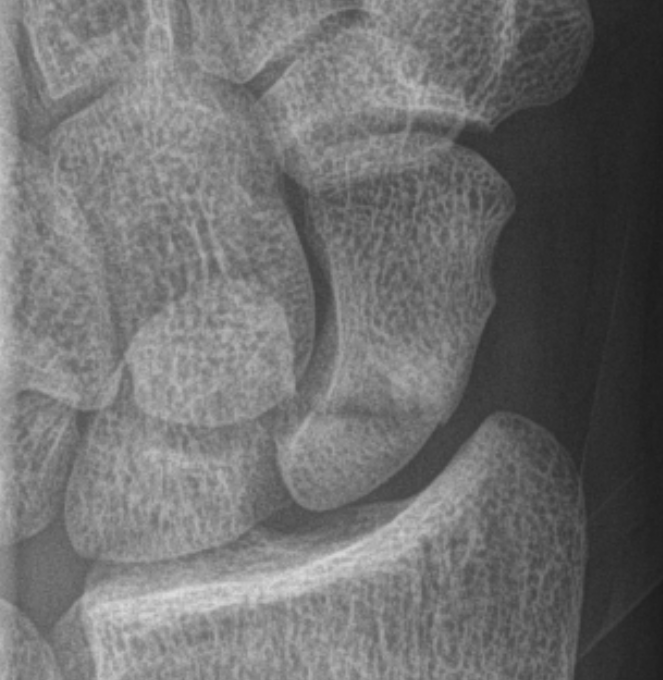

Scaphoid waist fracture 1 mm displaced

Scaphoid fracture with significant displacement

Scaphoid proximal pole fracture